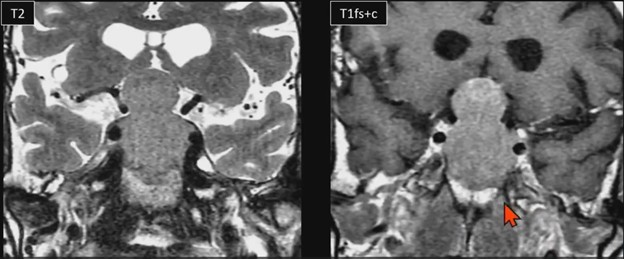

The Snowman Sign—Pituitary Macroadenoma

60-year-old with progressive vision loss for years, elevated prolactin

Waist Deep: When viewing a coronal or sagittal MRI of a classic pituitary macroadenoma (PM), you’ll often spot a snowman-shaped, homogeneously enhancing mass. This characteristic shape occurs due to a sella mass that develops a suprasellar extension, creating a “waist” as it pushes upward. In these pronounced cases, the normal pituitary tissue is usually completely displaced or obscured. You may also notice local bony involvement, including erosions in the sphenoid sinus and clivus.

Hat Trick: As the tumor extends superiorly, it exerts mass effect on the optic chiasm. The chiasm can become so severely stretched that it is difficult to visualize directly—effectively forming a sadly stretched “hat” resting atop our snowman’s noggin.

If the optic chiasm is too stretched to be seen clearly, look for the anterior cerebral arteries (ACA) and the anterior communicating arteries (Acomms). Because these vessels supply perforators to the optic chiasm, they are physically tethered to it. As these vessels are displaced superiorly by the mass, you can use ACA/Acomms as a reliable surrogate for location.